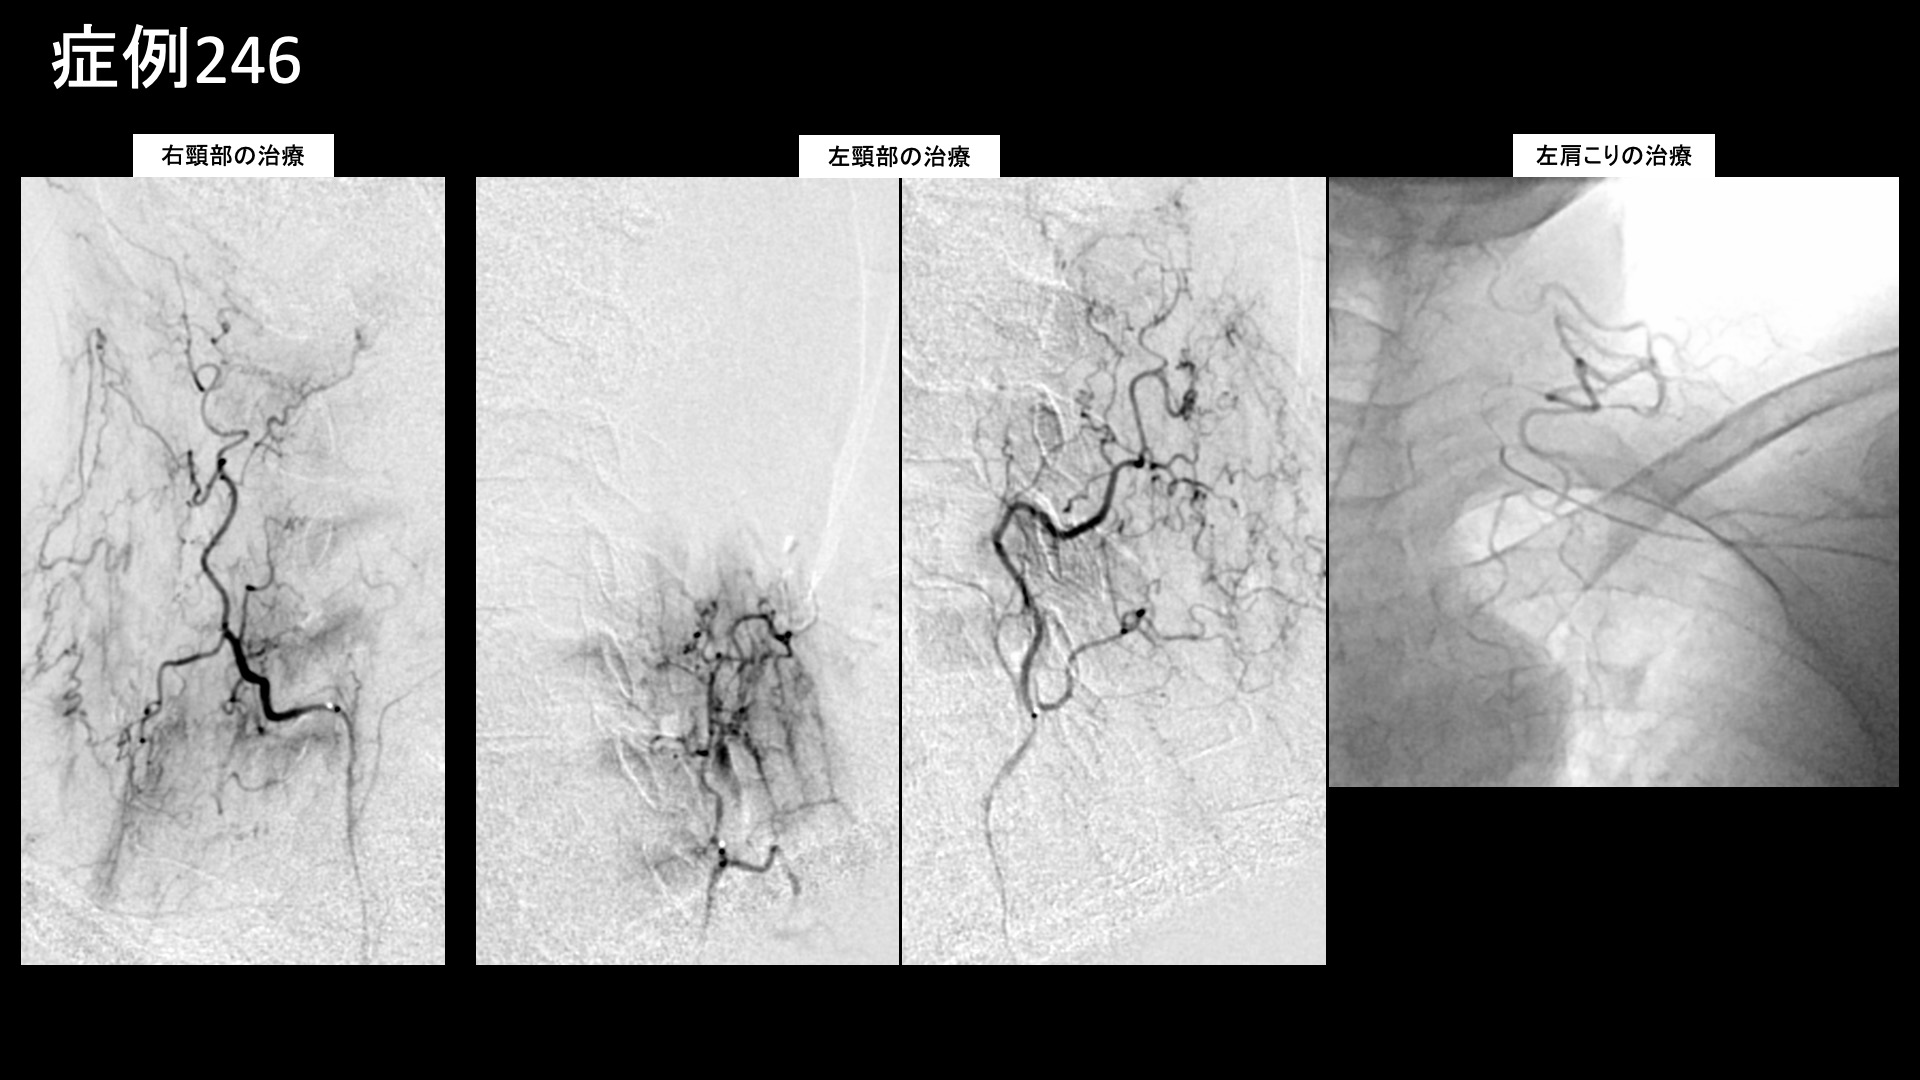

治療の所見

まず首肩こりの治療を行いました。血管造影を行うと、首こりの主要責任血管である深頸動脈、上行頸動脈筋肉枝などでモヤモヤ血管が濃染像として描出されました。肩こりの主要責任血管である頸横動脈、その他複数個所の血管を治療した後、頭部・顔面の治療を行いました。特に、後頭動脈でモヤモヤ血管が濃染像として描出されました。いずれも治療後は画像上速やかに消失しました。その他複数箇所の治療を行い終了しました。